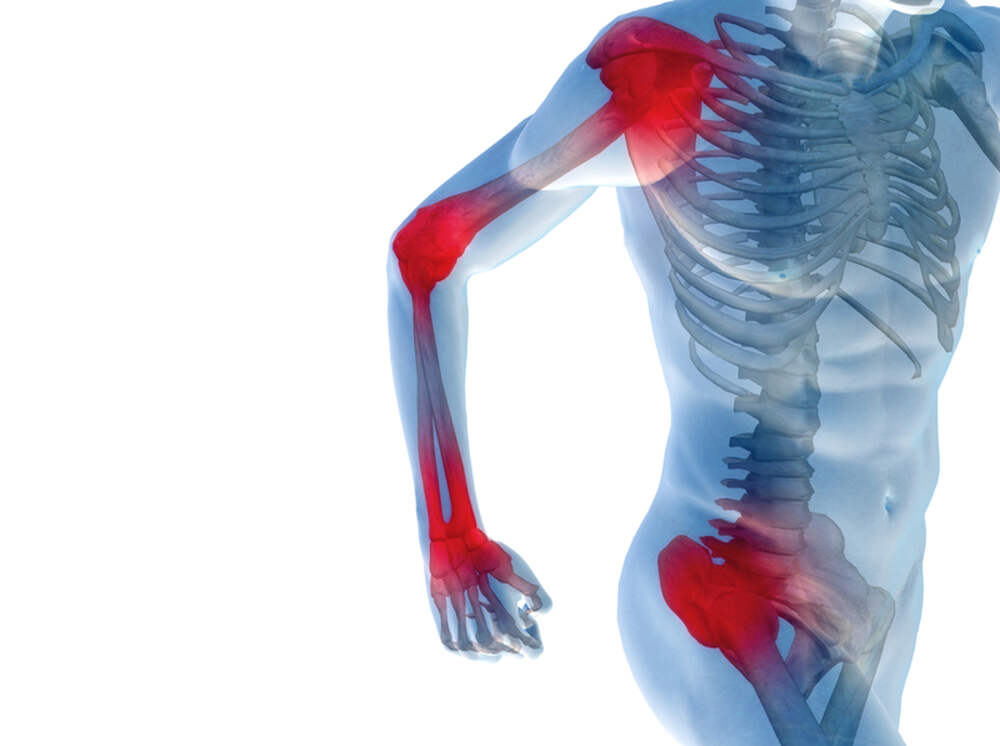

О чем говорит боль в суставах

Боль в суставах - что за ней стоит? Подробнее о воспалительных заболеваниях суставов.

Заболевания, сопровождающиеся болью суставов, можно разделить на три группы:

• околосуставные заболевания мягких тканей (тендинит, бурсит);

• полиартрит (острый, подострый, хронический) – воспаление нескольких